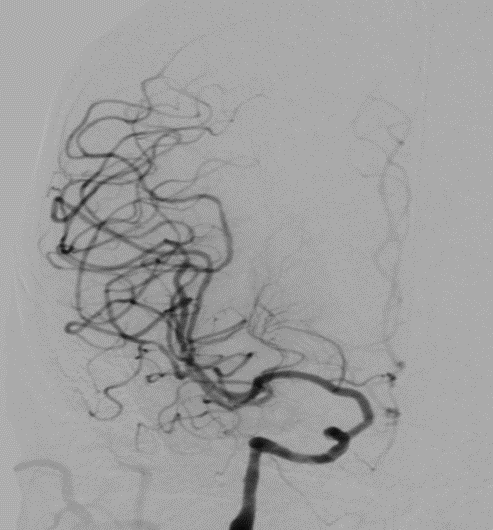

导丝怎么扩【载药时代 球扩天下】NOVA DES®颅内药物洗脱支架在颈内动脉颅内段重度狭窄的应用二例!_https://www.jmylbn.com_新闻资讯_第27张

DSA

重要影像结论:左侧颈内动脉C4段重度狭窄。

诊断

病变部位:左侧颈内动脉C4段